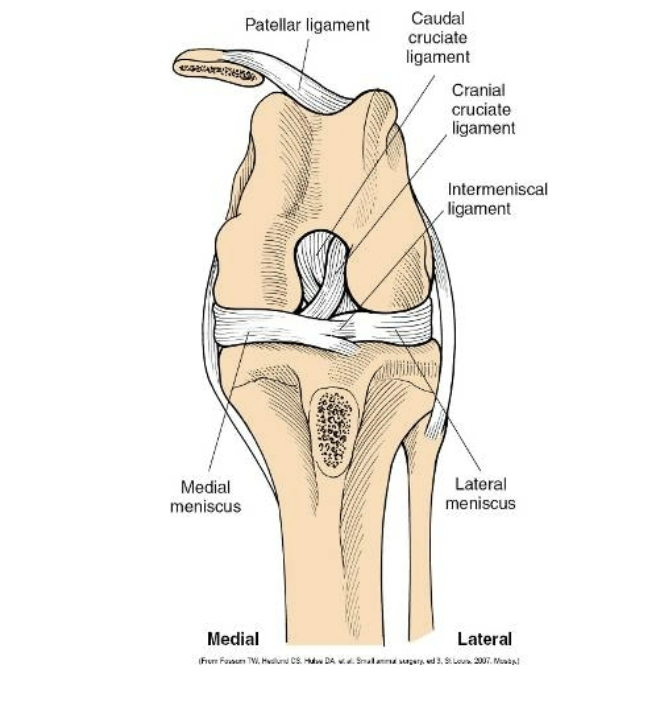

Cranial cruciate ligament rupture

One of the most common orthopedic problems

Usually caused by something

can be a partial or complete rupture

Very common to tear in the opposite leg